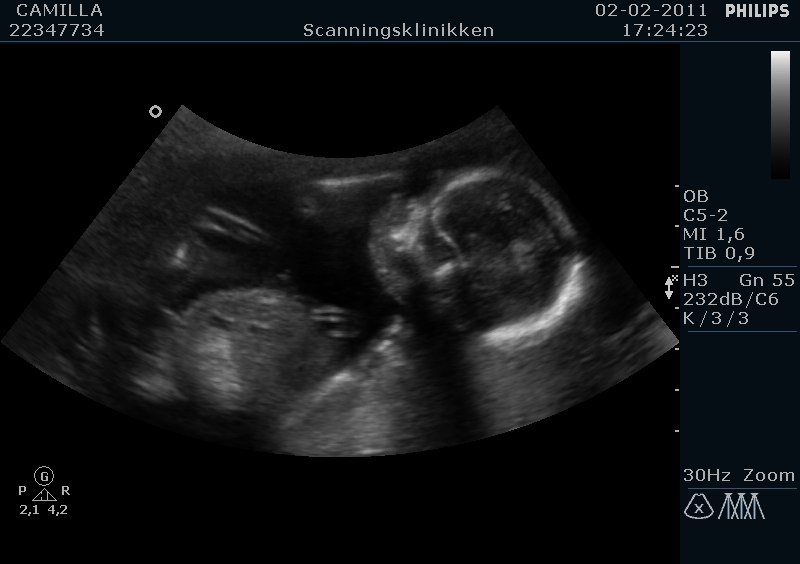

Hej alle sammen. Flertallet fik ret: Vi skal have en skøn lille dreng :-D :-D

Fik sgu tårer i øjnene da jeg fik øje på tappen! Så stort!

I får lige nogle billeder :-)

Tillykke med ham, hvor er det bare dejligt og hvor er han lille og fin på scanningsbillederne...

Ja er han ikke Vi fik hele 50 billeder på en cd rom, og så 5 stk i print